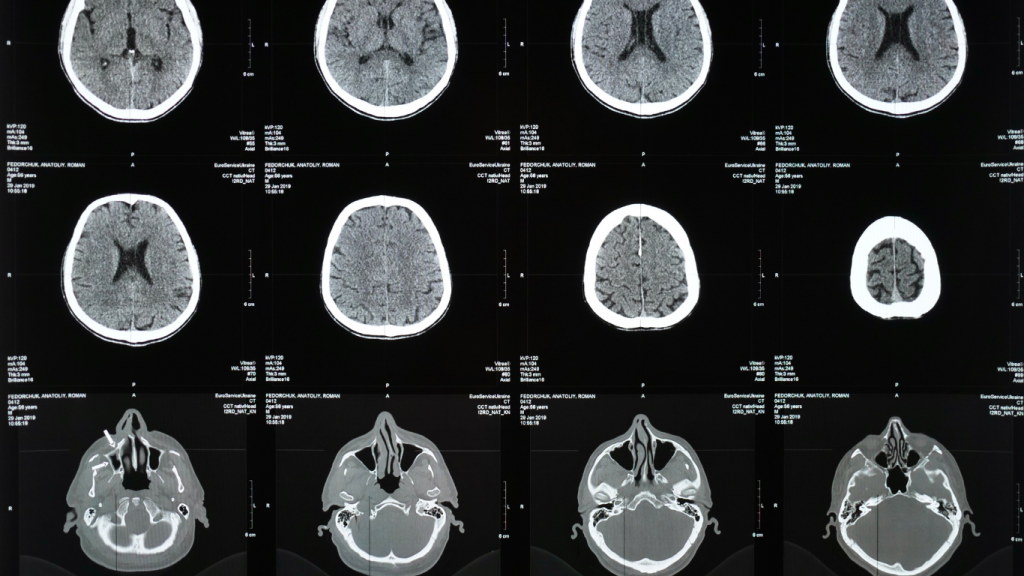

脑损伤是一种严重且复杂的伤害,可能对个人的身体、心理和生活质量产生深远影响。从轻微脑震荡到严重的创伤性脑损伤,这类伤害往往需要长期治疗和经济支持。在 Pace Law Firm,我们深知脑损伤对受害者及其家庭的巨大影响,并致力于为受害者争取公平和正义。

什么是脑损伤?

脑损伤(Traumatic Brain Injury, TBI)是指由外部撞击、冲击或其他外力导致的脑组织损害,常见的症状包括: